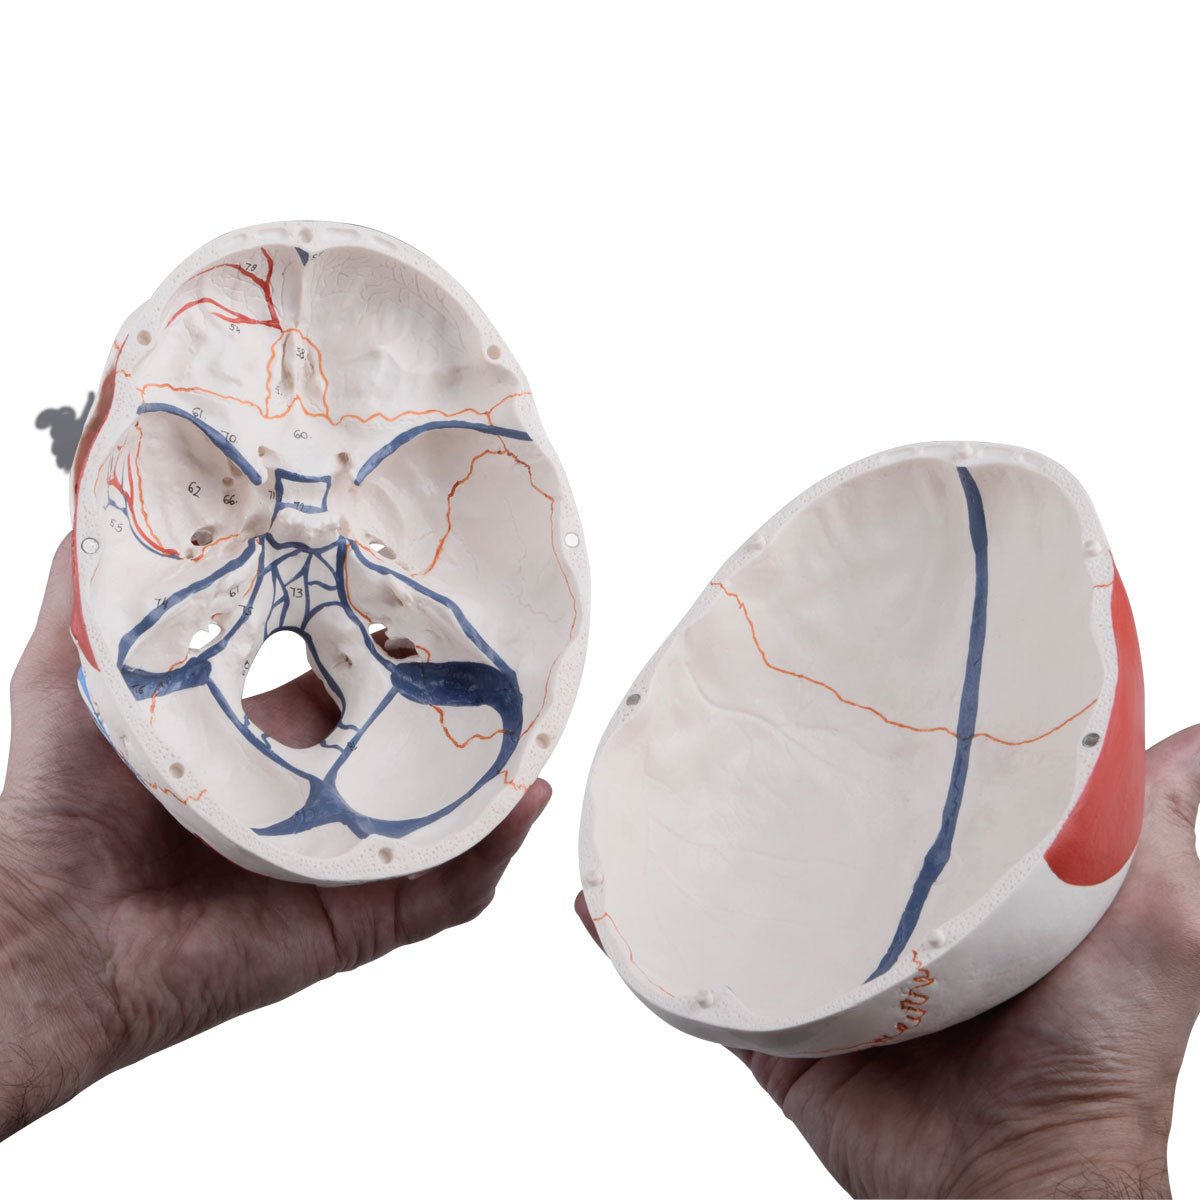

Selling anatomical models is the mainstay of eAnatomi, although we also spend a lot of resources developing our own anatomical materials such as posters. Anatomical models are used for various purposes and can show both defined tissues, organs and organ systems. Are you looking for a simple model of bone tissue or perhaps an advanced torso model based on MRI technology, you can find it all at eanatomi.com.